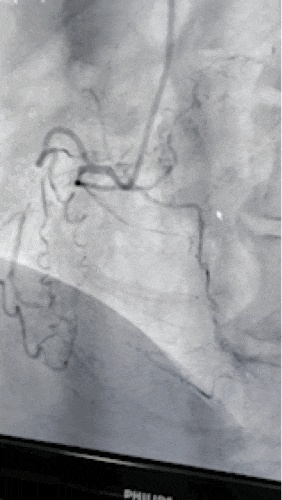

入院后,安排该患者完善相关检查,提示目前患者血管病变严重,左前降支近段狭窄70%-80%、粗大对角支近端90%狭窄,左回旋支中远段支架内完全闭塞,前向血流TIMI  0级,可见少量侧枝逆向血流,右冠状动脉中近段完全闭塞,前向血流TIMI  0级,可见同侧少量侧枝循环逆向血流。

9年前右冠脉为慢性闭塞病变,目前依然是CTO病变,但有少量自身侧枝循环,病变较前更加复杂了。

9年前在回旋支植入的2枚支架

目前支架内完全闭塞